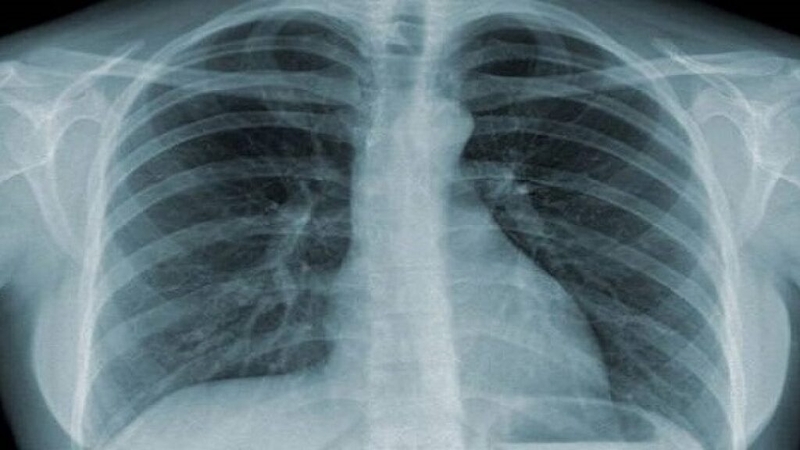

Xét nghiệm cyfra 21-1 là một công cụ quan trọng trong việc đánh giá và theo dõi bệnh nhân có nguy cơ cao về ung thư phổi. Protein cyfra 21-1, là một phần của protein cytokeratin 19, được tìm thấy trong tế bào của nhiều loại mô trong cơ thể, đặc biệt là tế bào phổi. Khi tế bào bị tổn thương hoặc chết, protein này được giải phóng và có thể đo lường trong máu.

Bình thường nồng độ protein cyfra 21-1 trong máu là < 3,3 μg/ml, Khi nồng độ này ở mức thấp, không có dấu hiệu đáng kể về sự tổn thương tế bào. Mặc dù cyfra 21-1 thường tăng cao trong trường hợp mắc ung thư phổi, nó cũng có thể tăng nhẹ ở một số bệnh lành tính, chẳng hạn như bệnh gan, suy thận và một số bệnh lý khác ngoài phổi. Đối với những trường hợp này, tăng nhẹ nồng độ cyfra 21-1 có thể được xem xét nhưng thường không lớn và không đặc trưng. Và đặc biệt, cyfra 21-1 tăng cao trong ung thư phổi, thường thấy nhất là ung thư phổi không tế bào nhỏ, có thể lên đến > 10,5 μg/ml.